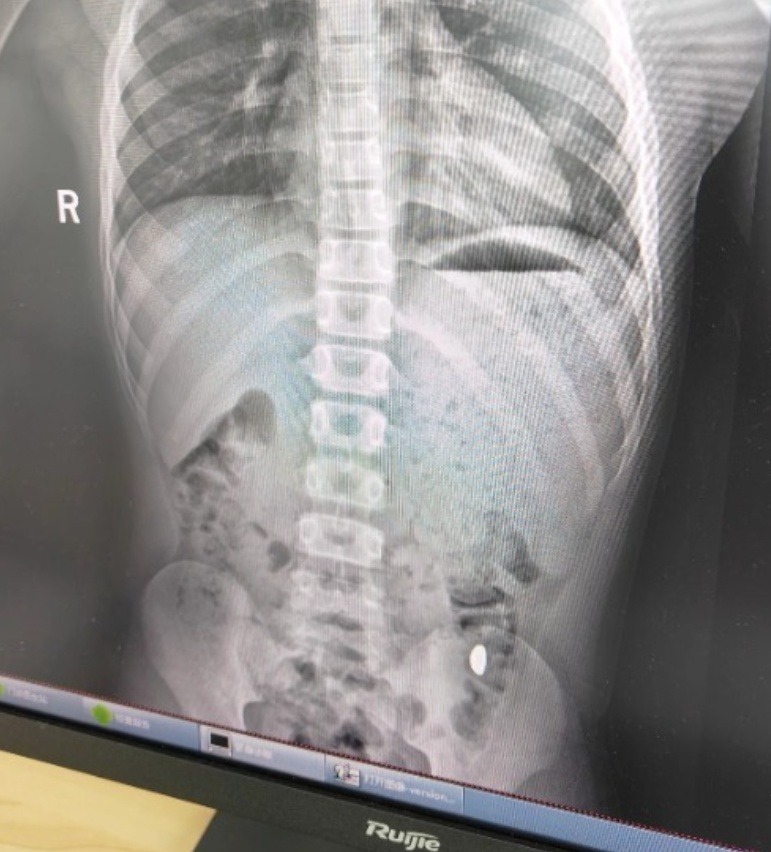

500.000 người theo dõi vụ cậu bé 11 tuổi nuốt nhầm miếng vàng 10g- Ảnh 2.

Ảnh chụp X-quang của cậu bé nghịch ngợm

Hồ sơ khám tại Bệnh viện Nhân dân số 5, thành phố Côn Sơn (Tô Châu) ghi nhận bệnh nhi nuốt nhầm khoảng 10 gram vàng, đã đi vệ sinh 2 lần nhưng chưa thấy vàng. Hiện tại không có đau bụng hay nôn ói, chẩn đoán cho thấy còn dị vật trong dạ dày. May mắn là, sau khi thăm khám buổi sáng, ngay buổi chiều hôm đó, vàng đã được thải ra ngoài.